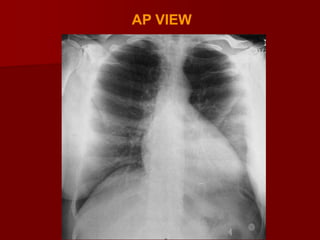

VIEWS OF CXR

P.A VIEW

AP VIEW

LATERAL VIEW

LATERAL DECUBITUS VIEW

LORDOTIC VIEW